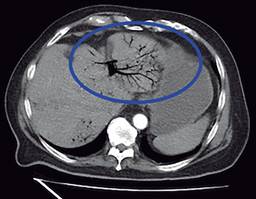

Masculino de 77 años con antecedentes de diabetes mellitus 2 e hipertensión arterial sistémica de larga evolución, antecedentes quirúrgicos de colecistectomía laparoscópica hace seis años y cateterismo cardiaco por cardiopatía isquémica crónica. Inicia su padecimiento actual 10 días previos a su ingreso con cuadro de dolor abdominal difuso en cuadrantes inferiores, así como ataque al estado general acompañado de astenia e hiporexia. Fue manejado por facultativo externo con antibioticoterapia. A su llegada al Servicio de Urgencias se presenta con taquicardia y tendencia a la hipotensión acompañado de alteración del estado de alerta. A la exploración física se palpa plastrón inflamatorio en cuadrante inferior izquierdo que despierta dolor a la manipulación del mismo, sin embargo, no hay datos de irritación peritoneal, sus laboratoriales con leucocitos 13,400 mm3, neutrofilia 92.9% y lactato de 3.9 mmol/l. Se solicita tomografía abdominopélvica contrastada en donde se muestra trombosis de la vena porta (Figura 1), neumatosis portal (Figura 2) y enfermedad diverticular (Figura 3), por los hallazgos anteriores se da manejo inicial con soluciones intravenosas y antibioticoterapia empírica de amplio espectro con piperacilina-tazobactam 4.5 g IV cada 8 horas, posterior al manejo estabilizador se realiza laparotomía exploradora, en donde se realiza sigmoidectomía y colostomía terminal debido a los hallazgos de perforación diverticular (Figuras 4 y 5) y plastrón inflamatorio purulento en el mesosigmoides con especial distribución en el trayecto de la vena mesentérica inferior, se toma cultivo y se maneja el posoperatorio en terapia intensiva, se deja antibioticoterapia dirigida a E. coli. Se calcula nutrición parenteral total y se inicia terapia anticoagulante con enoxaparina 60 mg subcutáneos (SC) cada 12 horas. El paciente cursó con evolución clínica favorable gracias al manejo multidisciplinario que se brindó. Egresó a la semana del procedimiento quirúrgico sin complicación alguna, se cita a consulta externa una semana después de su egreso tolerando vía oral con estoma funcional y con la herida afrontada. El reporte de histopatología reveló enfermedad diverticular complicada.